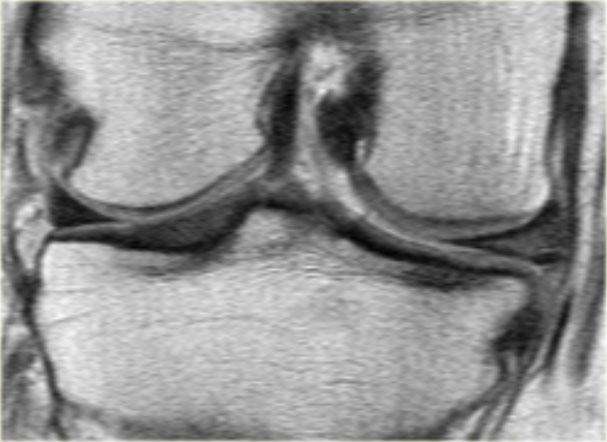

Cùng ca bệnh trên với hình ảnh mặt phẳng sagittal.

Lưu ý phần bị rách của sụn chêm chạy ra phía trước qua hố gian lồi cầu (các mũi tên)

- Thông thường chỉ có hai cấu trúc chạy trong hố gian lồi cầu. Ở đây chúng ta thấy dây chằng chéo sau bình thường.

- Dây chằng chéo trước bình thường.

- Phần bị rách của sừng sau như là ‘cấu trúc thứ ba’

trong hố gian lồi cầu. - Phần bị rách chạy ra phía trước.

- Phần bị rách nhập vào sừng trước và giả tạo hình ảnh rách dọc ở sừng trước.

Lưu ý phần còn lại nhỏ của sừng sau.